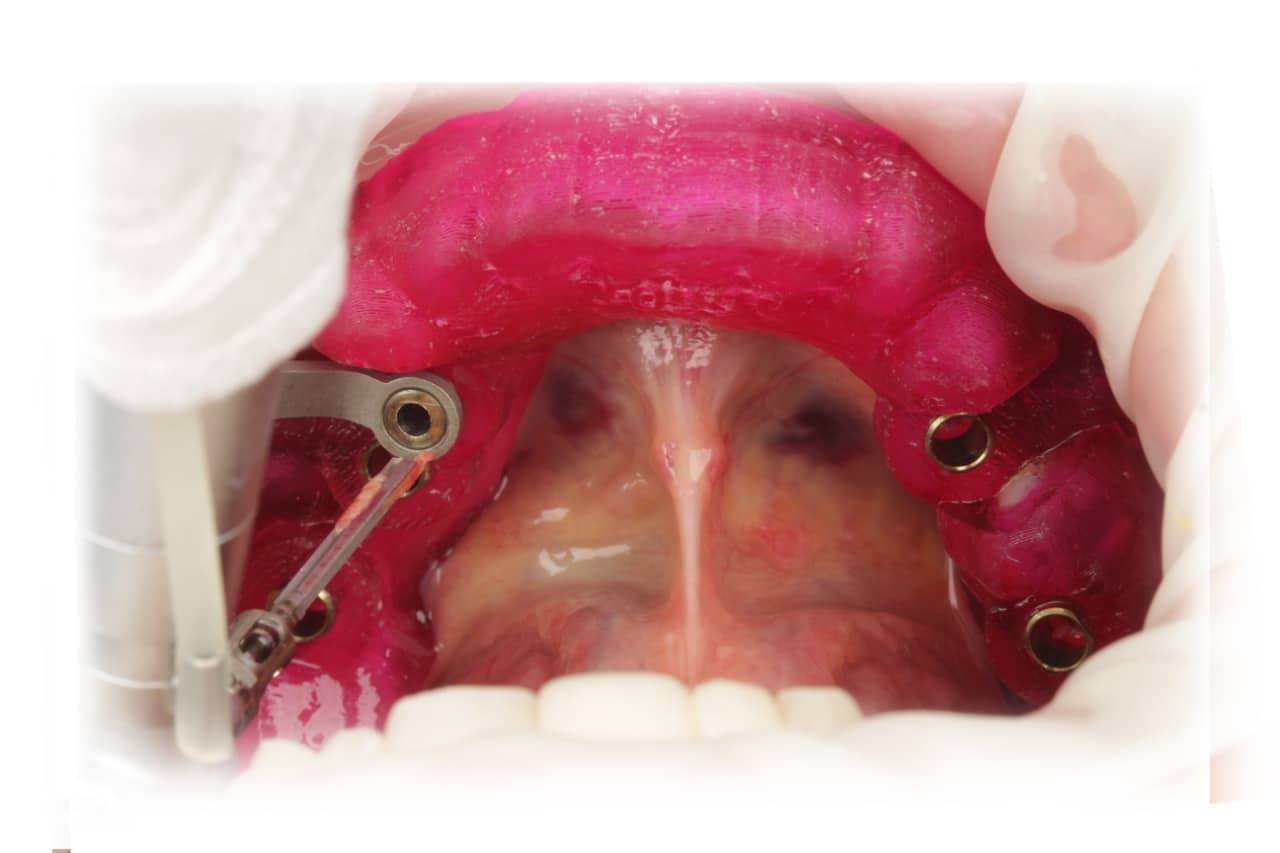

Cirurgia Guiada por Dr. João Marcelo Arcoverde

Adepto à filosofia de trabalho de que menos é mais, Dr. João Marcelo Arcoverde se tornou pioneiro no Brasil ao unir a técnica que permite repor dentes perdidos sem a necessidade de cortes e uso de bisturi convencional que diminuem drasticamente a necessidade de enxertos ósseos.

A Cirurgia Guiada é uma técnica inovadora, cujo implante dentário é feito sem cortes e pontos, portanto gerando maior conforto ao paciente, seja na reposição de um dente, de vários ou de todos.